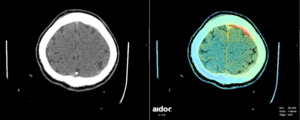

In the TMC Emergency section, Aidoc’s radiology AI solution sifts through CT images, automatically identifying potential critical findings, such as acute intracranial haemorrhages or acute/incidental pulmonary emboli. The solution has shown high accuracy and ease of use which leads to more accurate reports, increased reader confidence and potentially fewer missed pathologies. This is especially valuable as it can help to point to very subtle and critical findings that could be overlooked. Once the case has been processed by AI, the cases with findings are flagged in the reporting platform (Optemis) and the status of the exam is raised so that the case will be picked up sooner.

Aidoc highlightings a subdural haematoma (red color).

Aidoc highlightings a subdural haematoma (red color).